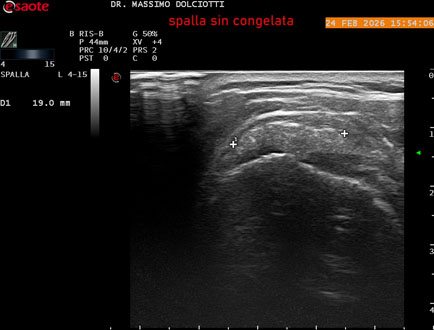

Data inserimento: 02/03/2026

Ecografia del: 24/02/2026

Strumento: Esaote MyLab Eight

Sonda: Lineare Multifrequenza 4-15 MHz

Età Paziente: F 71 anni

Motivazione dell'esame: da 1 mese dolore alla spalla sinistra, anche di notte.

Commento all'esame: le immagini ed il video documentano il tendine sovraspinato sinistro spiccatamente disomogeneo, per presenza di immagine iperecogena, delle dimensioni di 21 x 4 mm, da ricondurre a estesa calcificazione. Quadro clinico di spalla congelata.

Conclusioni: spalla sinistra congelata (frozen left shoulder).

In collaborazione: Dr.ssa Marica Manfredi - Ancona, Dr. Ilir Qose - Ancona

Presentazione: Dr. Massimo Dolciotti - Ancona

Elaborazione digitale: Andrea Dini - Ancona